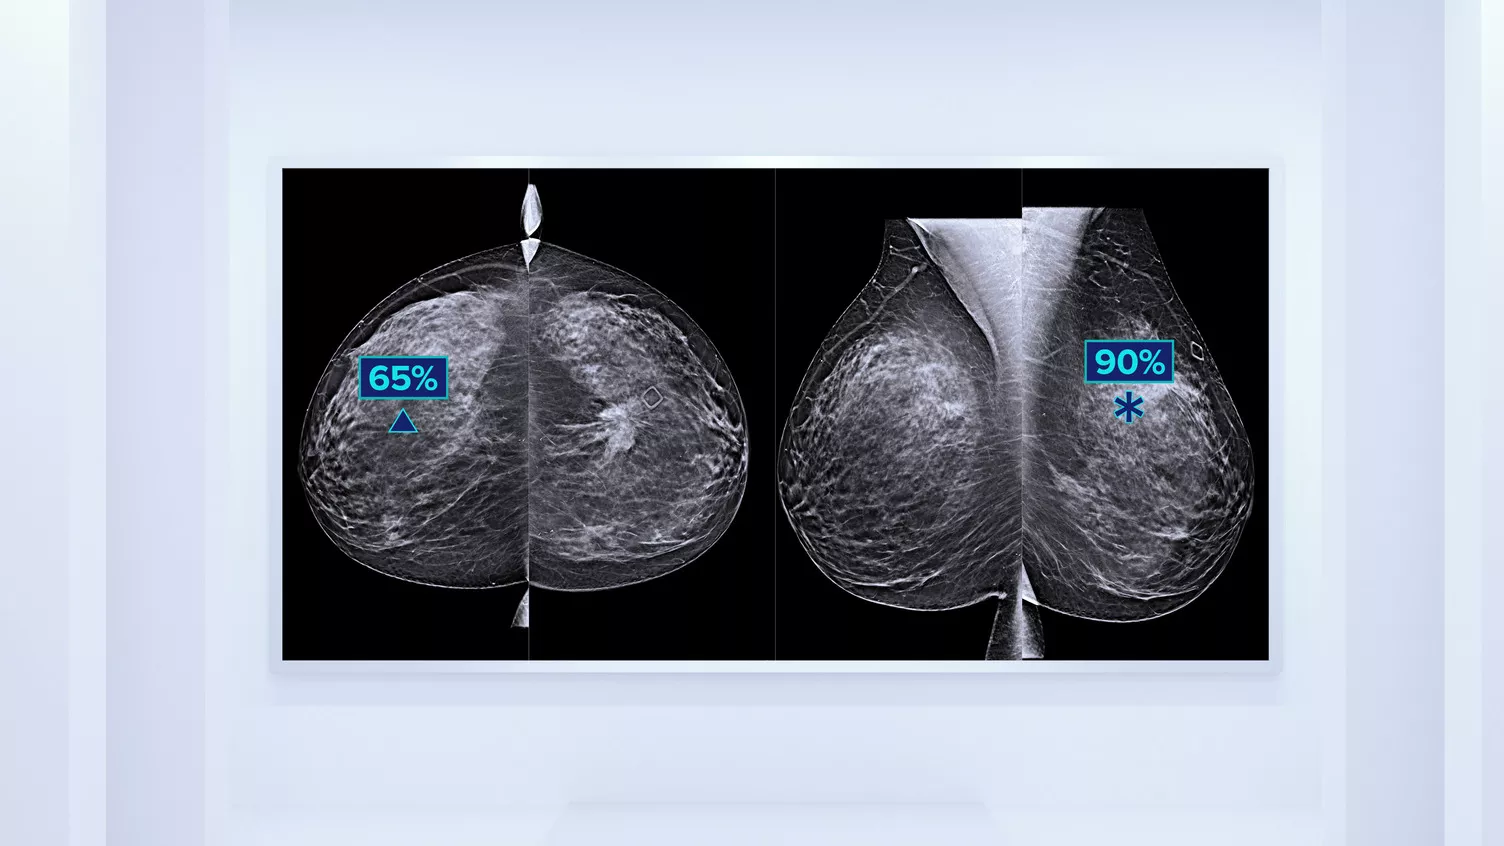

Better Risk Prediction

In addition to volume, pattern and texture of fibroglandular tissue may play just as an important role in mammographic cancer risk prediction.3-5 By analysing and categorising breast texture and pattern, our technology can deliver the accurate information you need to achieve more consistent and reliable scoring and confidently design patient-specific screening.